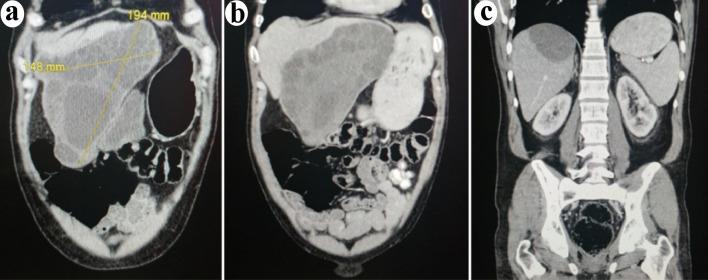

We present a case of immune thrombocytopenic purpura (ITP), which leads to the diagnosis of severe cystic echinococcosis. Our patient presented with platelets of 5 × 10/L, and investigations uncovered multiple large echinococcal hepatic cysts, the largest of which measured 19.4 × 15 × 12 cm, and peritoneal implants. While initially refractory to prednisone and immunoglobulins, the ITP responded to dexamethasone. The echinococcosis was treated with albendazole followed by surgical resection of all lesions. Our patient's disease course has evolved favorable since his initial treatment with an isolated episode of recurrent thrombocytopenia 2 years later, and has remained in remission for the past 2 years. While a causal association between echinococcosis and ITP cannot be confirmed, this case is a reminder of the importance of remaining inquisitive for atypical potential triggers of ITP. We also present a review of the limited literature on the association of parasitic infections and ITP.

我们报告一例免疫性血小板减少性紫癜(ITP)病例,该病例最终诊断为严重囊性棘球蚴病。我们的患者血小板计数为5×10/L,检查发现多个巨大的肝棘球蚴囊肿,其中最大的囊肿尺寸为19.4×15×12厘米,并且存在腹膜种植转移。虽然最初对泼尼松和免疫球蛋白治疗无效,但ITP对地塞米松有反应。棘球蚴病采用阿苯达唑治疗,随后对所有病灶进行手术切除。自最初治疗以来,我们患者的病程进展良好,仅在2年后出现过一次血小板减少复发,并且在过去2年一直处于缓解状态。虽然棘球蚴病与ITP之间的因果关系无法确定,但该病例提醒我们对于ITP非典型潜在诱因保持探究的重要性。我们还对关于寄生虫感染与ITP关联的有限文献进行了综述。